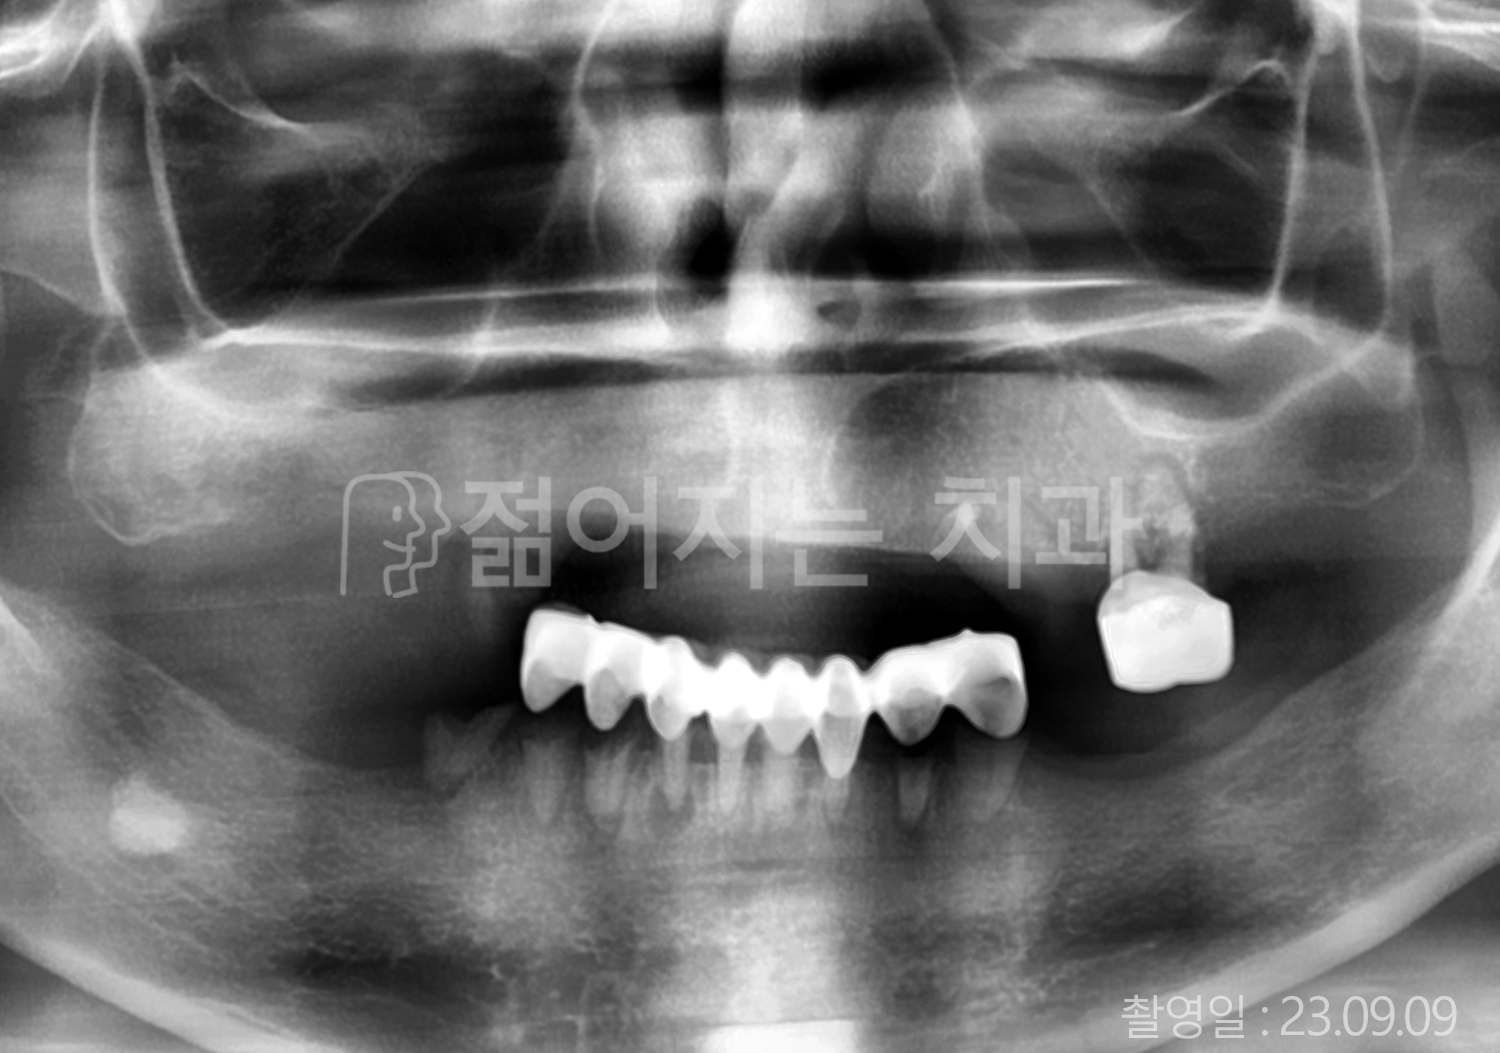

• 60대 전체치아 10개 이상 임플란트